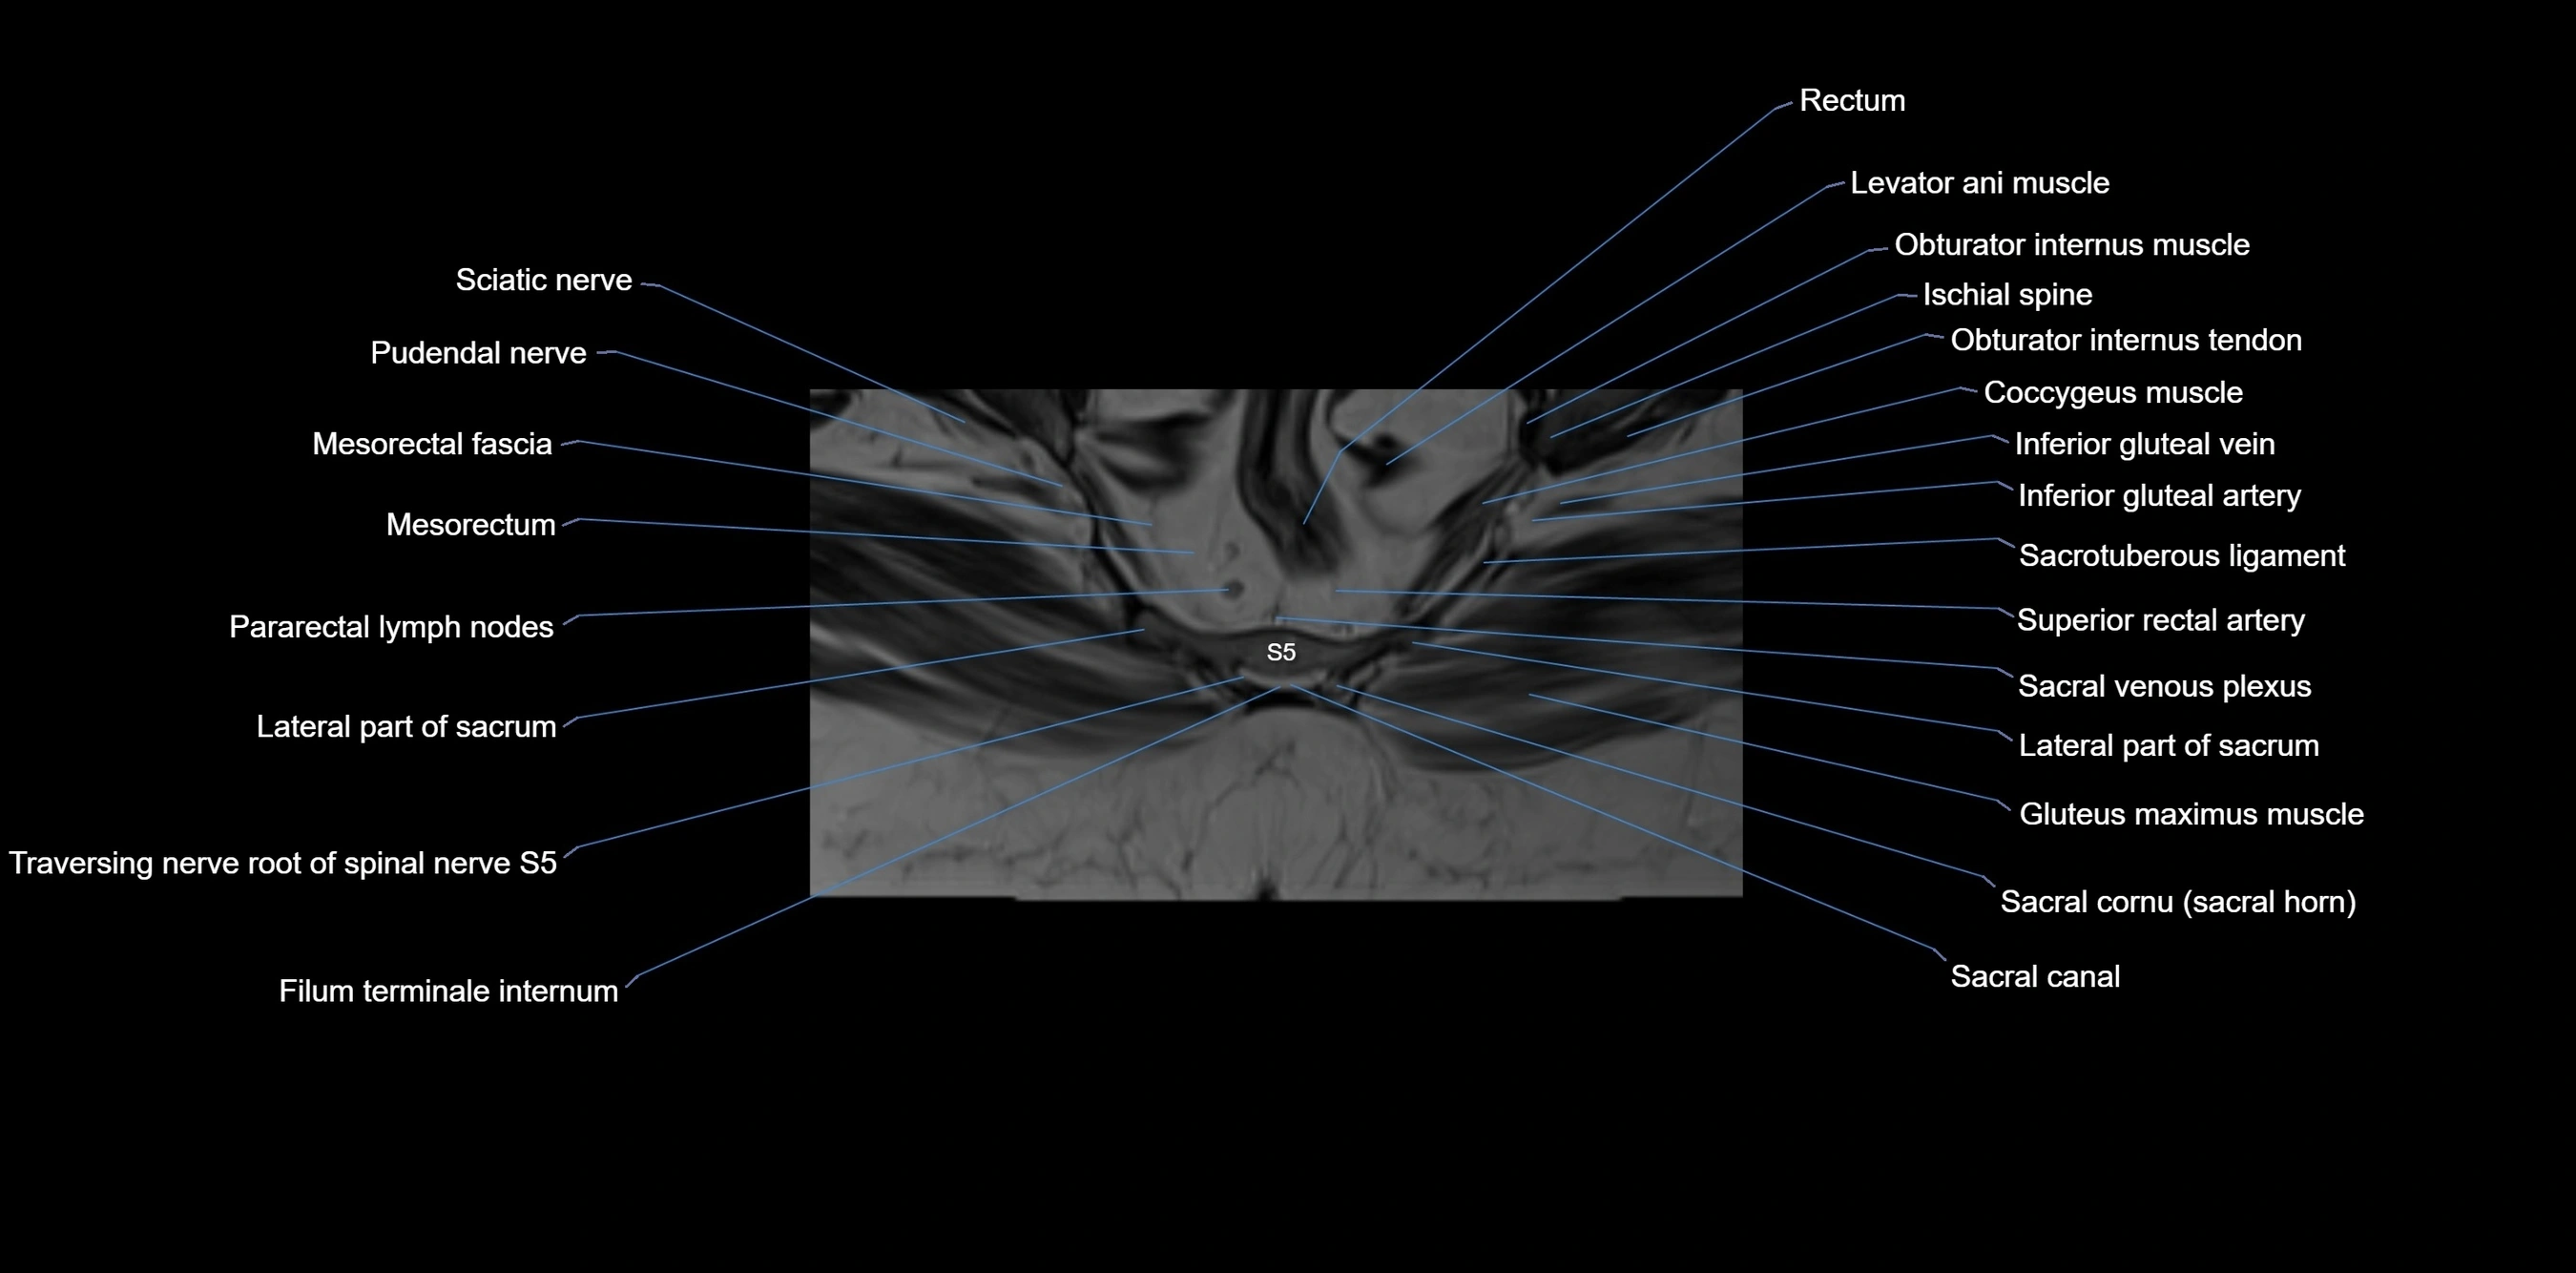

CT VRT image

image